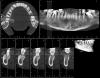

pakulino Опубликовано 8 октября, 2013 Поделиться Опубликовано 8 октября, 2013 Уважаемые коллеги пацыентка 32 года. Пришла поправить прикус сняли панорамку потом томографию ситуацыя не из легких что посоветуете? Ссылка на комментарий

Sahan Опубликовано 8 октября, 2013 Поделиться Опубликовано 8 октября, 2013 17,28,38,47,48 на вынос. Со всем остальным можно работать. Чистка, вектор, открытый кюретаж с GBR плюс Эмдогейн. Далее ,через пару месяцев повторная оценка и составление окончательного плана лечения. Лечение будет недешевым, без 100% гарантий, требующим постоянной поддерживающей терапии иначе все станет еще хуже чем до начала лечения. Однако шансы продлить жизнь зубам хорошие. 2 Ссылка на комментарий

carloss Опубликовано 8 октября, 2013 Поделиться Опубликовано 8 октября, 2013 17,28,38,47,48 на вынос. Со всем остальным можно работать. Чистка, вектор, открытый кюретаж с GBR плюс Эмдогейн. Далее ,через пару месяцев повторная оценка и составление окончательного плана лечения. Лечение будет недешевым, без 100% гарантий, требующим постоянной поддерживающей терапии иначе все станет еще хуже чем до начала лечения. Однако шансы продлить жизнь зубам хорошие. даже 16 осталяем?.. это после Исландии такой консервативный подход? Нет я в общем то согласен, разумно, и раньше много увлекался, даже без использования ауто и эмдогейма, с ними результат будет получше, но как Вы отметили всё равно без гарантий и - постоянная поддерживающая терапия, к тому же пища будет застревать.. а нужно ли, и какой плюс? Ссылка на комментарий

Sahan Опубликовано 9 октября, 2013 Поделиться Опубликовано 9 октября, 2013 (изменено) даже 16 осталяем?.. это после Исландии такой консервативный подход? Нет я в общем то согласен, разумно, и раньше много увлекался, даже без использования ауто и эмдогейма, с ними результат будет получше, но как Вы отметили всё равно без гарантий и - постоянная поддерживающая терапия, к тому же пища будет застревать.. а нужно ли, и какой плюс?А где там 16 зуб? Его же нет.)) Разные случаи бывают. Была у меня как то пациентка 34 лет , провессиональная танцовщица нар танцев со значительно худшей ситуацией. Так там 100% нужно было все удалять. Но она категорически отказывалась от предложенного лечения. Ей очень важно было сохранить свои зубы. Поэтому она ушла и попала к мему товарищу, который не был так категоричен. В итоге через время они совместно все таки пришли к предложенному мной плану лечения, но это уже было не в моей клинике)). А вообще важно услышать , что хочет пациент. Да, после Исландии мое видение поменялось сильно. Там кстати разбирался подобный клинический случай. Самый агрессивный подход был , кстати , у русской группы)) Изменено 9 октября, 2013 пользователем Sahan 1 Ссылка на комментарий